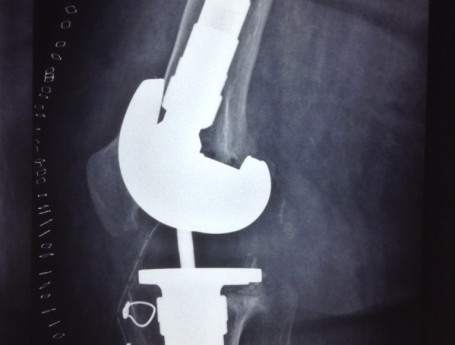

Revision Total Knee Replacement After a fructure

• Revision Total Knee Replacement After a fructure